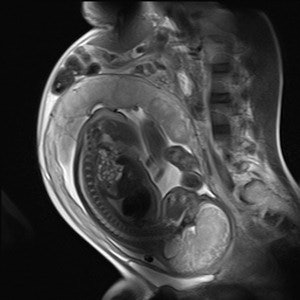

Fetal MR spectroscopy can assist with in utero measurements of fetal cerebral lactate concentrations. It may provide information on the adequacy of fetal oxygenation, and can help with decision-making on the optimal time of delivery. This figure shows fetal localizers used for spectroscopy measurements. Image courtesy of  Janet De Wilde, PhD, and C. McComb."In the pre-examination questionnaire for determination of pregnancy, it is important to ask two questions: What was the first day of your last complete menstrual period? To the best of your knowledge, are you pregnant, or do you think you could be?" he said during last year's ECR refresher course on pregnancy.